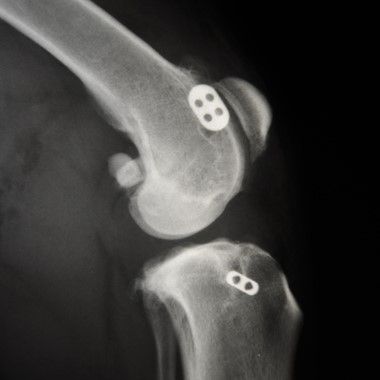

Orthopädische, Knochen-, Gelenks-Chirurgie

Orthopädische, Knochen- &

Gelenks-Chirurgie

Auch bei Kreuzbandrissen, Knorpeldefekten sowie bei Frakturbeandlungen bieten wir die passenden Opeartions- und Behandlungsmethoden an.

implantat gelenk

Goldimplantation

Diese Methode wird in erster Linie zur dauerhaften Schmerztherapie bei chronischen Gelenksbeschwerden eingesetzt.